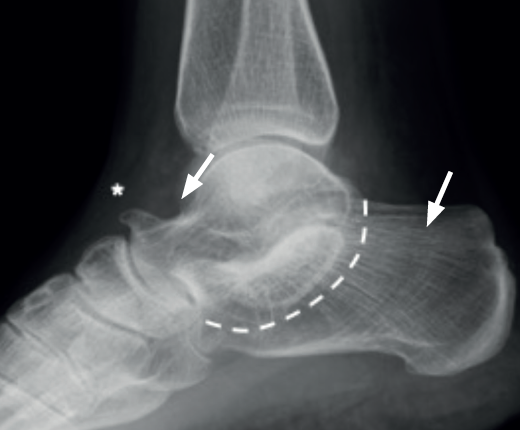

El pico del astrágalo (talar beak) se produce secundariamente por la rigidez del retropié(45). La articulación de Chopart aumenta su movilidad a dorsal, el escafoides sube por encima de la cabeza del astrágalo creando con la tracción capsular un pico (es más común en las TC que en las CN) (Figura 7).

El signo de la C o C-sign es el signo directo más fácil de identificar en la vista lateral. Analizando la faceta medial de la articulación subastragalina en las coaliciones TC, que son las más frecuentes (Figuras 7 y 8). Si es distrófico o la línea articular es irregular, sugiere osteoartritis. Los pacientes suelen ser jóvenes al diagnóstico. Posteriormente, en caso de sinostosis con continuidad entre el calcáneo y el astrágalo, un bloque óseo une la voluminosa faceta medial distrófica al sustentaculum tali. Tiene la forma de un arco convexo posteriormente: de ahí el “signo de la C”(45). En pies planos puede ser positivo sin coalición(46) (sensibilidad del 88% y especificidad del 87%)(22).

La ausencia de la faceta medial (subastragalina) precisa de una proyección exacta lateral centrada en el retropié(22). Si la articulación subastragalina posterior es visible y bien alineada, la anterior debiera ser igualmente visible; si no, es posible una coalición(22,47) (sensibilidad del 72-100% y especificidad del 42-94%) (Figura 8A).